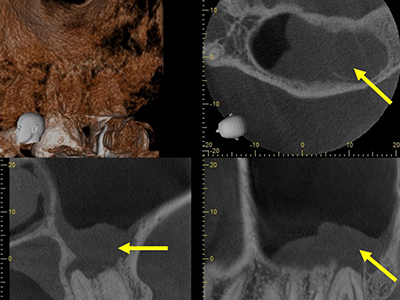

また、すべての治療時に必ずサージカルルーペ(拡大鏡)を使用し、ケースに応じてマイクロスコープおよびCTを使用しています。口腔内は非常に狭くて暗く、特に臼歯部(奥歯)は見えにくいため、裸眼では精密な治療は困難です。CTは従来のレントゲン撮影では分かりえない3次元的な診査・診断が出来るため、より難易度の高い治療を可能にします。

3次元的な診査が可能なCT

3次元的な診査が可能なCTは正確な診断をするのに無くてはならないです。

CT画像

根管の数や湾曲、根尖病巣の大きさなど、レントゲンでは分からない多くの情報をCTはもたらしてくれます。